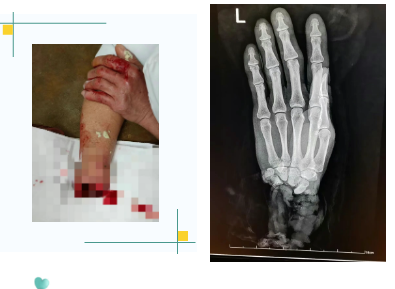

患者为48岁食品厂工人,在操作机器时不慎被搅面机绞伤,导致右手腕完全离断。赶到医院时,陪同人员怀中的毛巾里,一只沾满面粉、苍白干瘪的手掌令医护人员着实揪心:断端处肌腱、血管与神经缠绕,血迹已凝固。

“快!立即启动创伤急救流程!”王恬一边引导患者进入检查间,一边向上级医师汇报。她迅速完成加压止血与无菌包扎,与此同时,医院绿色通道全面开启:麻醉科、手术室、输血科、后勤车队迅速响应,备血、调车、准备器械……一场与时间的赛跑就此开始。

晚22:40,随着最后一针缝合完成,移植的静脉逐渐泛起红润——血流恢复了!离体十余小时的右手手指慢慢显现血色,指腹逐渐饱满。手术室外,家属紧紧握住医护人员的手,泪水夺眶而出:“谢谢你们,真的谢谢……”

术后,患者生命体征平稳,再植手掌血运良好,末梢红润,标志着再植手术获得成功。据医疗团队介绍,患者病情稳定后,预计功能恢复将是一个长期过程,可能需要一年以上时间。